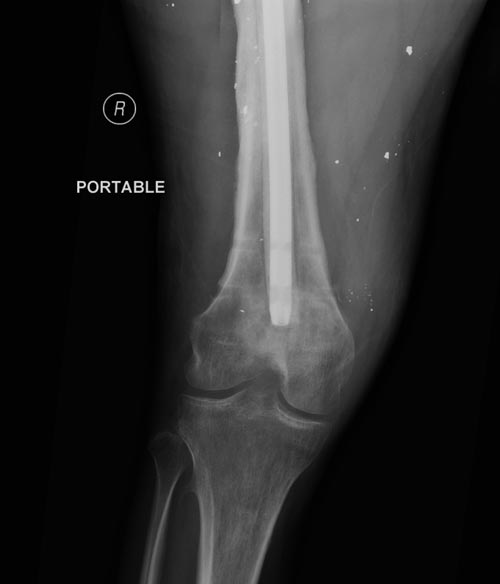

На снимках осложнение огнестрельного перелома бедра поздней инфекцией. 7

лет назад оперирован: правое бедро, сперва на ExFix, затем заменен на

гвоздь, а левая - гвоздь при поступлении.

Беспокойство проявил недавно, по поводу жалоб на боли сделано МРТ и

дренирование абсцесса терапевтами. Мы удалили гвоздь, сделали I&D,

Рекомендуется: антибиотический гвоздь на цементе. Нагрузку можно

разрешить сразу, перелом сросся давно!